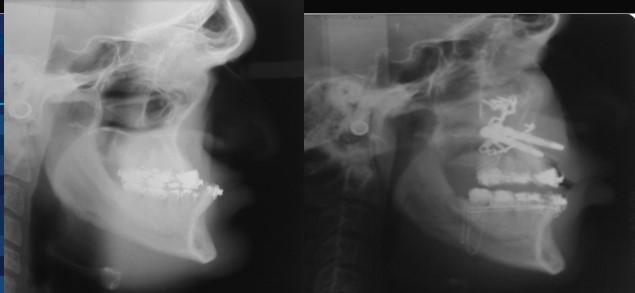

For over 30 years, Dr. Guerrero has made it his mission to improve the lives of his patients through specialized surgical care that restores function and comfort. Dr. Guerrero’s work embodies precision, compassion, and a dedication to patient well-being. Corrective jaw surgery is one of the advanced services offered, designed to address functional issues and enhance the quality of life for those who need realignment and reconstruction.